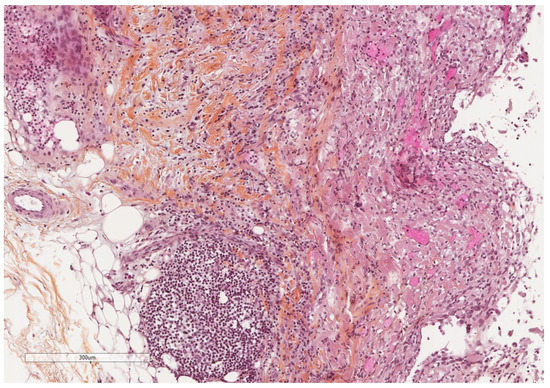

- Karpathiou, G.; Hathroubi, S.; Patoir, A.; Tiffet, O.; Casteillo, F.; Brun, C.; Forest, F.; Rahman, N.M.; Peoc’h, M.; Froudarakis, M.E. Non-specific pleuritis: Pathological patterns in benign pleuritis. Pathology 2019, 51, 405–411. [Google Scholar] [CrossRef] [PubMed]